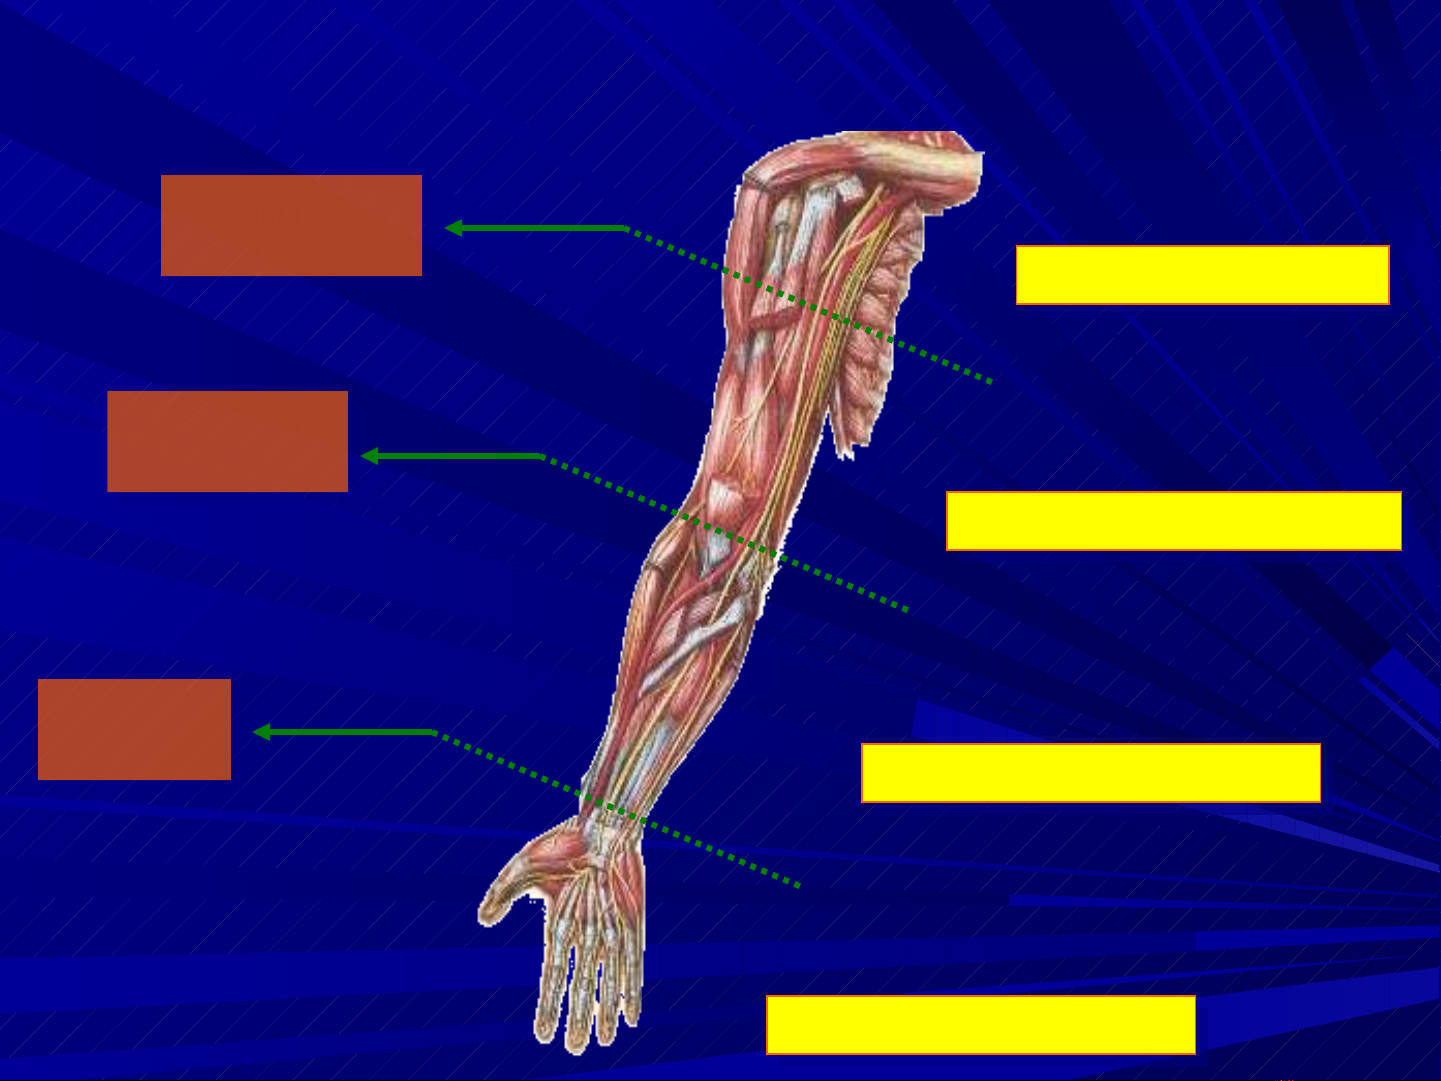

Đ NG M CH CÁNH TAYỘ Ạ

Đ NG M CH CÁNH TAYỘ Ạ

Đ NG M CH C NG TAYỘ Ạ Ẳ

Đ NG M CH C NG TAYỘ Ạ Ẳ

Đ NG M CH BÀN TAYỘ Ạ

Đ NG M CH BÀN TAYỘ Ạ

B D IC Ờ ƯỚ Ơ

NG C L NỰ Ớ

B D IC Ờ ƯỚ Ơ

NG C L NỰ Ớ

CÁCH N PẾ

KHU U 3cmỶ

CÁCH N PẾ

KHU U 3cmỶ

N P G PẾ Ấ

C TAYỔ

N P G PẾ Ấ

C TAYỔ